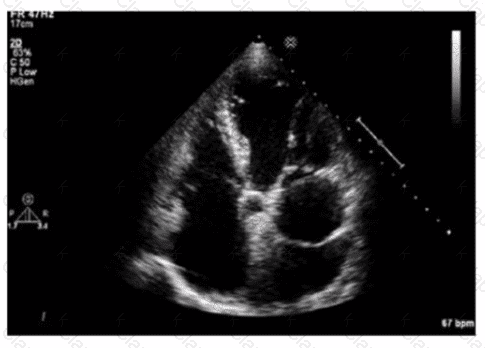

Which diagnosis is most likely confirmed by echocardiography in a 65-year-old female presenting with new onset chest pain associated with ST segment elevation on the electrocardiogram and angiographically normal coronary artenes?